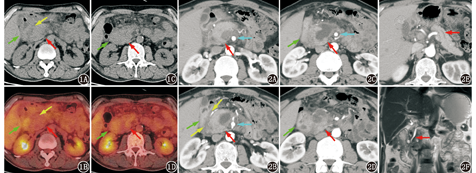

患者男,48岁,于饮酒后出现间断上腹痛、背痛3个月余。实验室检查提示血常规、肝肾功正常,血清淀粉酶290 (括号内为正常参考值范围,下同;25~115) U/L,血清脂肪酶1 294 (73~393) U/L,血清癌胚抗原(carcinoembryonic antigen, CEA;0~5 μg/L)、糖类抗原(carbohydrate antigen, CA)19-9 (0~37 kU/L)、免疫球蛋白(immunoglobulin, Ig)G亚类均正常。腹部超声提示胰头囊实性占位,大小约4.7 cm×2.7 cm,壁上见多处乳头状突起,边界欠清,彩色多普勒血流显像(color Doppler flow imaging, CDFI)未见明确血流信号。外院腹部增强CT提示胰头占位并周围渗出,周围局部包裹性积液,病变周围多发稍增大淋巴结。腹部18F-脱氧葡萄糖(fluorodeoxyglucose, FDG) PET/CT显像结果、MRI及增强CT图像见图1,图2。

18F-FDG PET/CT可见胰头部明显肿胀,周围脂肪间隙模糊,有可疑的占位,胰头部FDG代谢不均匀,但未见明显增高,最大标准摄取值(maximum standardized uptake value, SUVmax)2.5;胰头与十二指肠降部间的间隙消失,十二指肠亦有肿胀表现,肿胀的十二指肠降部肠壁代谢较其余节段的十二指肠略高,SUVmax 2.6;此外胰头周围可见多发淋巴结,直径<1 cm,FDG代谢未见明显增高。腹部增强CT可见胰头部明显增大,有囊实性病变,形态不规则,囊内有分隔和突起,胰头部实性部分有多处强化减低区,胰腺颈体尾部胰管轻度扩张,肠系膜上动脉周围有低密度影包绕,十二指肠降段肠壁增厚、水肿,肠壁可见多发小囊状低密度区。

上述胰腺肿瘤中,除胰腺导管腺癌外,其他肿瘤大多边界清,周围脂肪间隙亦清晰。本例胰头病变周围有明显的模糊渗出影,因此鉴别的焦点为胰腺导管腺癌与胰腺炎。本例符合胰腺癌表现的地方包括FDG代谢可不高、远端胰管有扩张、病变周围脂肪间隙模糊、肠系膜上动脉周围有低密度影包绕、胰周有多发淋巴结。不支持胰腺癌的地方包括病变位于胰头部且范围较大但尚未见明显的胆总管扩张,临床亦无梗阻性黄疸的表现,有饮酒病史诱发,血清淀粉酶、脂肪酶升高而肿瘤标志物正常。除以上特征外,本例还有十二指肠肠壁明显肿胀,代谢活性较正常十二指肠略高的表现,增强CT还可见十二指肠壁多发小低密度灶,另外胰头与十二指肠间的沟槽状区域(即胰头背侧、十二指肠降部和胆总管下段间的潜在间隙,内界为胰头,外界为十二指肠降段浆膜层,前界为十二指肠球或胃窦,后界为十二指肠水平段或下腔静脉)有条片状低密度区(图1A,图1B,图2A,图2B)。以上表现实际上是沟槽状胰腺炎(groove pancreatitis, GP)的特点,本例支持该诊断的理由包括以下几点:

1.GP是一种特殊类型的慢性胰腺炎,多见于40~50岁中年男性,起病多隐匿。GP的发生与十二指肠异位胰腺、胰腺分裂等原因导致的十二指肠副乳头解剖学异常或功能性障碍、长期饮酒有关[1],其机制是十二指肠副乳头解剖学异常或功能性障碍使胰液经副胰管排出不畅而淤滞在胰腺背侧,导致沟槽区炎性反应。长期饮酒可使十二指肠Brunner腺体增生并压迫十二指肠小乳头,使副胰管胰液排出不畅,同时过量饮酒可使胰液黏稠度增加,胰液排出受阻,因此长期饮酒也是GP的诱因之一。本例患者起病前即有饮酒史,且沟槽状区域有病变(图1A,图1B,图2A,图2B),与之相符。

2.GP较为特征性的表现是十二指肠壁内的小囊性病灶[2],可能为十二指肠内异位胰腺组织慢性炎性反应和胰管扩张,也可能与副胰管扩张有关[3,4]。本例增强CT即可见十二指肠降段肿胀,肠壁多发小囊状低密度区(图2D),此外PET/CT见十二指肠降部代谢略高(图1,绿箭头示)可能与十二指肠壁的慢性炎性反应有关。

3.本例无明显黄疸的临床表现,CT仅见胰管轻度扩张,胆总管扩张不明显,MRI见胰头内胆总管中下段渐进性、向心性变窄(图2F,红箭头示),系沟槽状区域内增生的炎性纤维组织包绕压迫胰头区的胆总管所致,受累的胆总管节段较长,与胰头癌、胆管癌的胆总管突然截断、上游胆管明显扩张的表现有所不同。临床上GP也多无黄疸或黄疸症状较轻,与胰头癌进行性加重的黄疸表现不同。此外,由于沟槽区增生的炎性纤维组织也可累及胰管周围,因此也有远端胰管轻度扩张的表现(图2E,红箭头示),这一点与胰头癌表现较为相似。

4.本例胰头病变周围脂肪间隙密度增高,并可见低密度影包绕肠系膜上动脉(图2A,图2B,图2C,蓝箭头示),病变周围可见多发淋巴结影(图像未显示),GP和胰腺癌中均可出现这种征象,此征象不易鉴别两者。增强CT、MR见到脉管内癌栓为诊断胰腺癌的有利证据,而GP为血管外压性改变,血管内无侵犯。